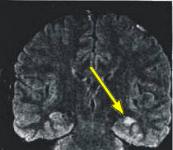

MRI FINDINGS: MRI detects mesial temporal sclerosis by demonstrating size asymmetry and abnormal signal within the atrophied hippocampus. Thin-section, high-resolution oblique coronal MR images are best for detecting these abnormalities, which can be subtle. Heavily T1-weighted images (Fig. 1) are best for detecting size asymmetry of the hippocampal gyri, while T2-weighted images (Fig. 3) and particularly FLAIR (fluid attenuated inversion recovery) images are most sensitive for detecting signal abnormalities (Fig. 2). The above images demonstrate left hippocampal atrophy and mesial temporal sclerosis (arrows).